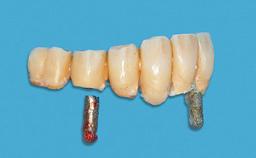

Mandibular Overdenture Supported by a CAD/CAM-milled Bar with Long Distal Extensions on Two Conventionally Loaded Implants

Abutment Type CAD/CAM

Prosthesis Type RDP